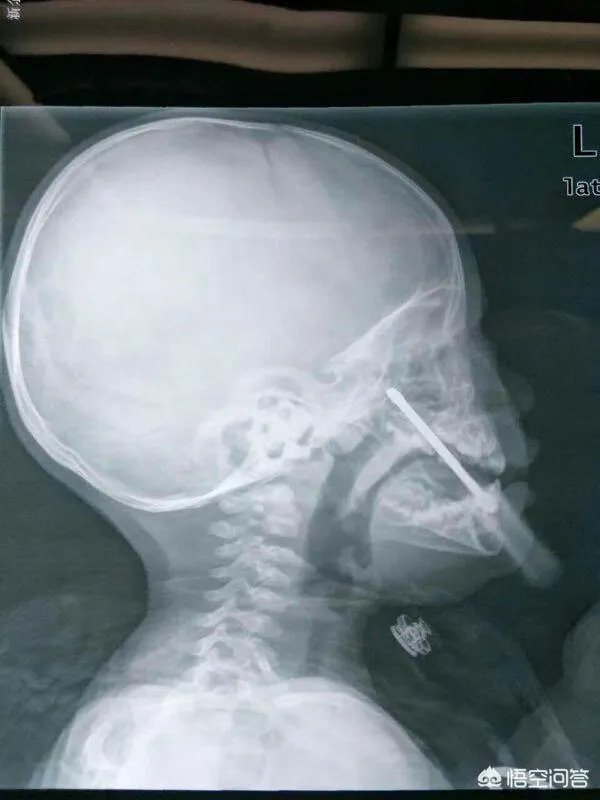

第二个病人是一个小孩子。那天中午我跟主任一起走路上班,进医院大门时碰到一个老奶奶抱着一个孩子大哭救命。我和主任跑过去一看,小孩子已经青紫,几乎没有呼吸,非常危急。从简短的交谈中知道孩子气管里卡东西了。主任抱起孩子跑去急诊科,命我赶快去拿气管插管的设备。我们科在9楼,我真是一口气跑上去,一口气跑下来拿来急救设备。到了急诊科及时把气管导管插进去。气管导管一插进气道,小孩子呼吸立刻好起来,嘴巴颜色也转红。最后卡住孩子气道的笔盖子被安全取出。说实话,如果当时孩子在大门口没有碰到我们,可能很难被救到。事后了解到孩子就住医院对面,父母和很多医院职工认识。孩子父母特地来医院感谢了好几次。

最后强调一遍,儿童气道异物和食道异物非常常见。大多是硬币,笔套,纽扣电池和花生瓜子,果冻等。父母尽量不要给孩子接触这些物品。万一出现气道异物可以使用海姆立克急救法办法(不建议没有经过训练的人员使用)。如果孩子呼吸困难,紧急送医。路上用力重拍儿童胸背上部(手掌拱起形成一个窝型)。如果没有呼吸特别困难,就尽量不要刺激小孩,平稳送医急救。